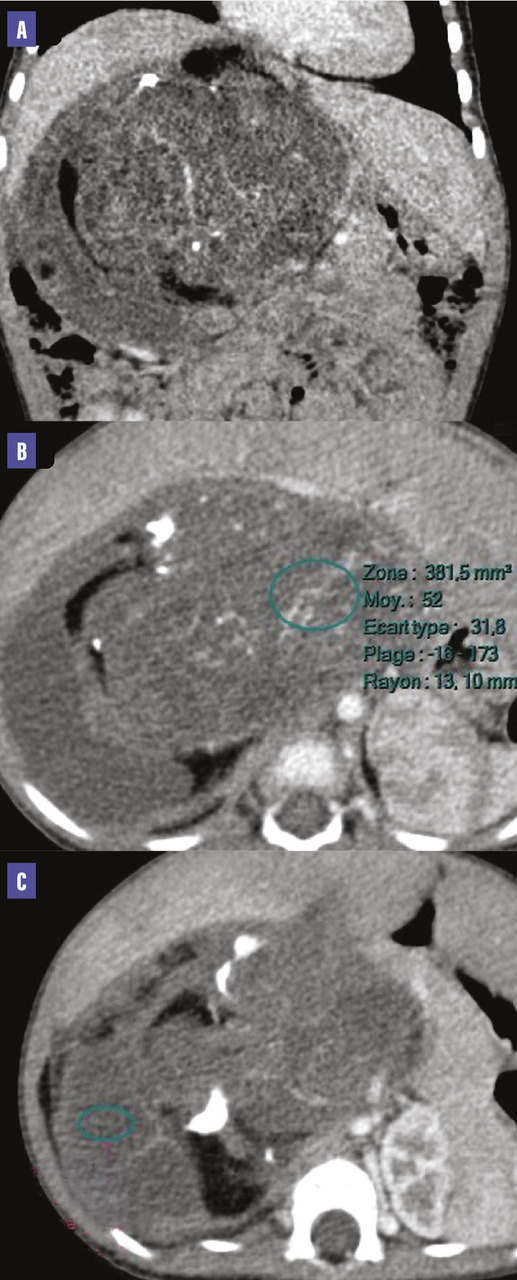

Un scanner abdomino-pelvien (figure) révèle une masse rétropéritonéale droite de 13 cm, bien limitée, à triple composante kystique, graisseuse et tissulaire, renfermant des calcifications, sans visualisation de la surrénale homolatérale. Cette masse dépend de la surrénale droite, selon les données opératoires.

Au scanner, le tératome se présente comme une tumeur à triple composante kystique, graisseuse et tissulaire. Un niveau liquide-graisse au sein de la lésion évoque un tératome mature, mais il est aussi décrit dans des liposarcomes bien différenciés.

Les calcifications sont fréquentes, caractéristiques lorsqu’elles sont présentes dans la paroi du kyste «rim sign» ou sous la forme de structures organisées (os, dents…).